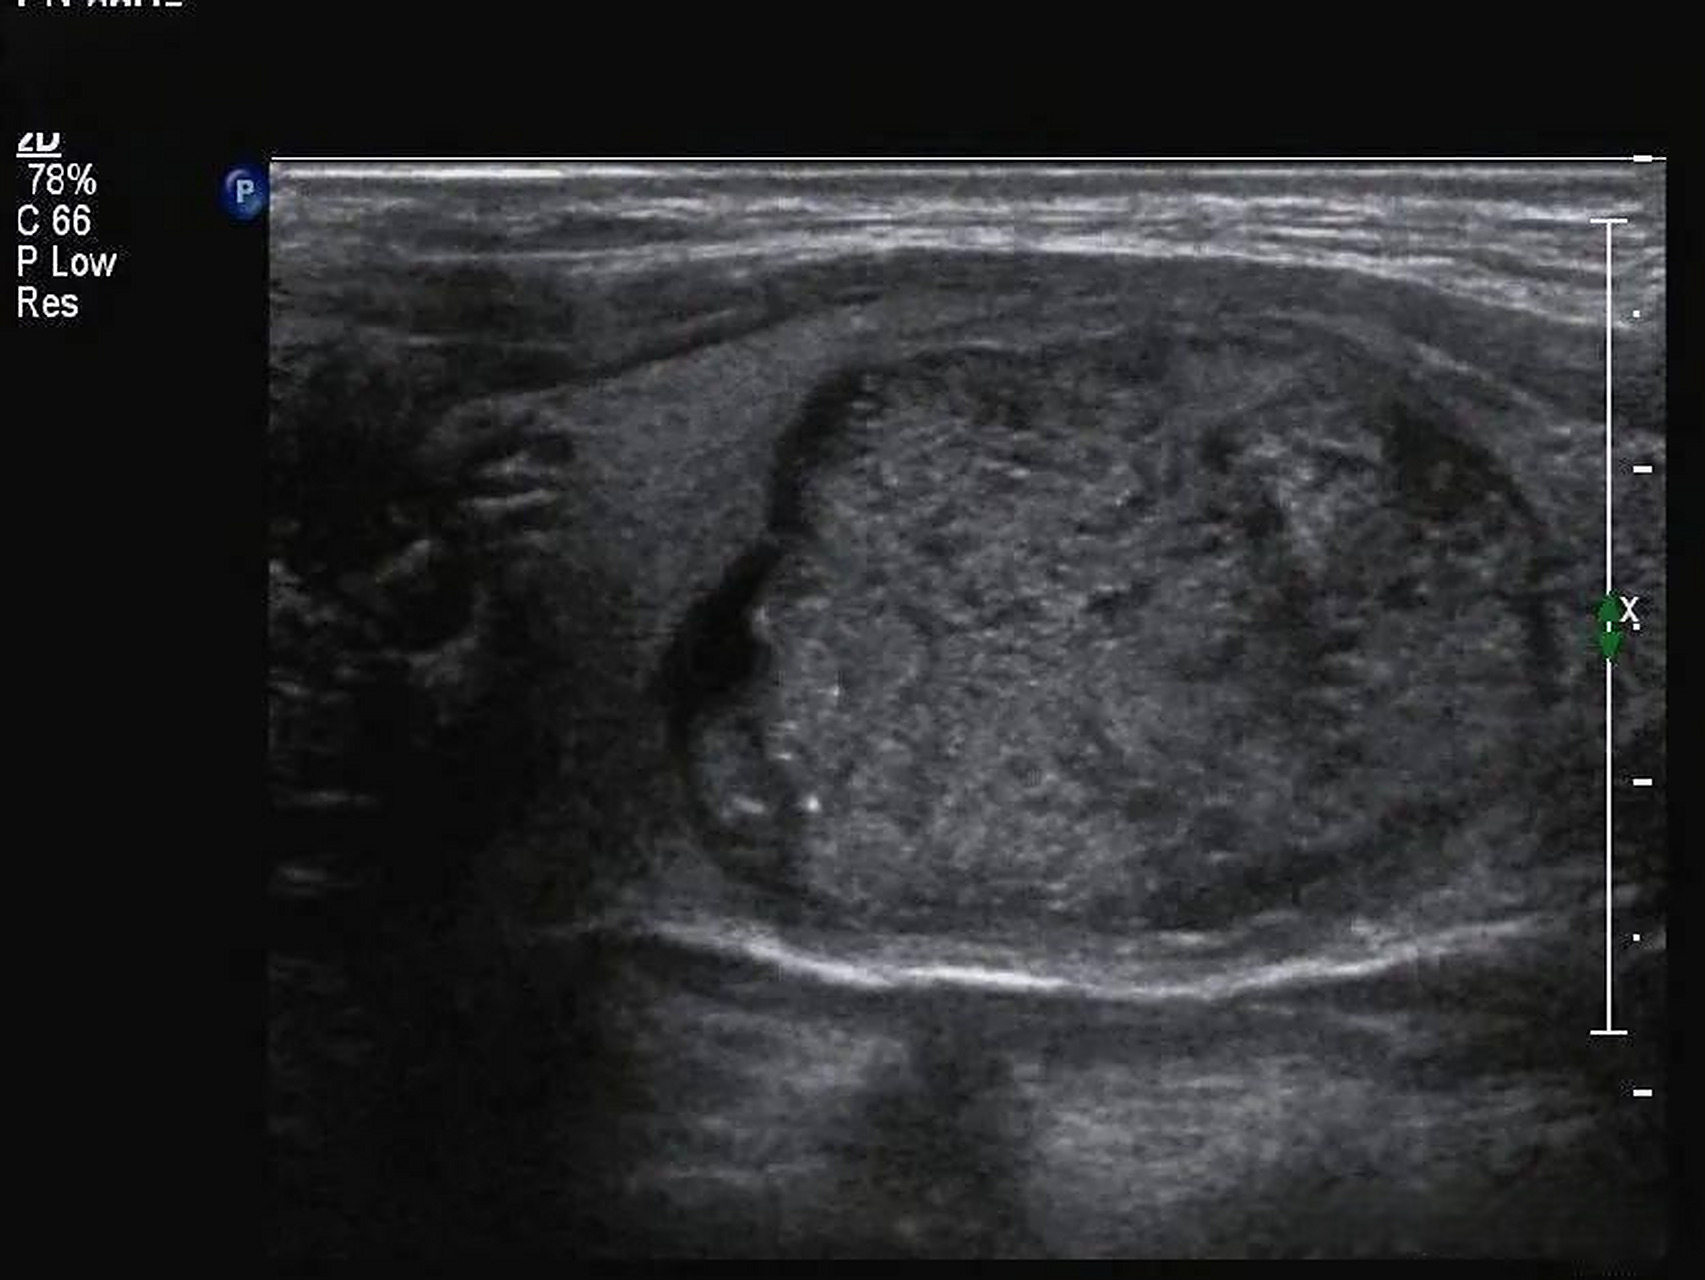

甲状腺结节

纵横比>1:恶性几率高甲状腺彩超低回声结节甲状腺结节超声甲状腺结节